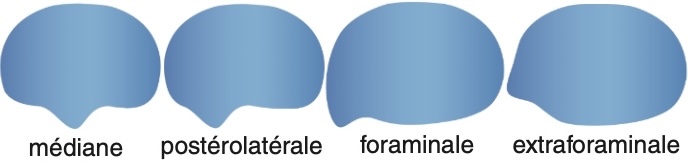

En L4-L5 : Etalement discal global avec composante foraminale, sans rétrécissement canalaire ou foraminal significatif ni argument en faveur d’un conflit discoradiculaire.

En L5-S1 : Etalement discal global avec composante foraminale, sans rétrécissement canalaire ou foraminal significatif ni argument en faveur d’un conflit discoradiculaire.